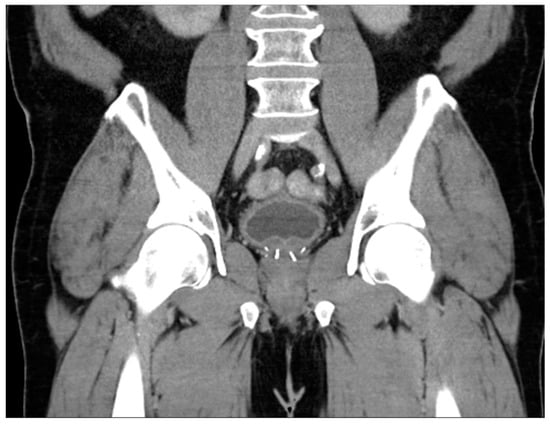

Figure 2. Axial T2 (A), diffusion-weighted b2000 (B), apparent diffusion coefficient (C), and dynamic contrast-enhanced (D) images of the pelvis demonstrating a focal ill-defined T2 hypointense lesion in the right midgland posterolateral peripheral zone with corresponding diffusion restriction and asymmetric enhancement, characterized as PI-RADS 5 per PI-RADS v2.1.

To briefly summarize the system, PI-RADS uses a grading scale from 1 to 5, wherein benign-appearing lesions receive a score of 1, and highly suspicious lesions are given a score of 5. The peripheral zone of the prostate is primarily assessed using diffusion-weighted sequences (DWI/ADC), where more convincing diffusion restriction is considered increasingly suspicious. In contrast, the transition zone is primarily assessed using T2-weighted sequences, where hypointense lesions are considered more suspicious as they become less circumscribed, homogenous, and with obscured margins, leading to suspicious lesions often being likened to “smudged charcoal” [28]. In both peripheral and transition zone lesions, maximal lesion diameter determines if a suspicious lesion is categorized as 4 or 5. DCE only impacts the overall scoring of a lesion in situations where a positive DCE can upgrade a peripheral zone lesion from 3 to 4. PI-RARDS v2.1 clarifies that DCE is considered negative if enhancement is diffuse, multifocal, does not correlate to a T2 or DWI abnormality, or if it does correspond to lesions compatible with BPH (Figure 2) [27]. While PI-RADS is also used during the setting of active surveillance, the Prostate Cancer Radiological Estimation of Change in Sequential Evaluation (PRECISE) score has also been developed to help standardize reporting of active surveillance cases and better stratify those who need or can avoid surveillance biopsy [45]. The PRECISE score is based on a 5-point scale where a score of 1 indicates the resolution of suspicious MRI features, 2 indicates a reduction in volume/conspicuity of MRI features, 3 indicates a stable MRI appearance, and scores of 4 and 5 demonstrate a significant increase in volume/conspicuity and/or definite stage progression [45]. Using this standardized approach, this initial study found that PRECISE scores of 1–3 have high NPV and can reduce the need for re-biopsy during active surveillance, while scores of 4–5 have moderate PPV and should be closely monitored or biopsied [45].